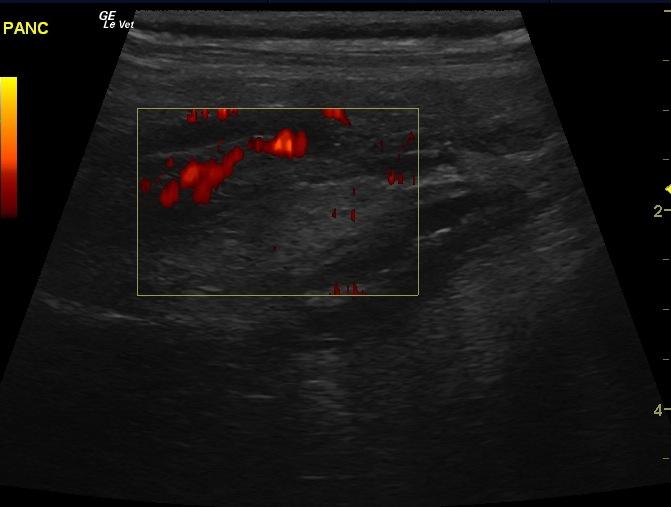

An 11 year-old MN Standard Poodle was presented for pyrexia, lethargy, and abdominal discomfort. Abnormalities on CBC and serum biochemistry were leukocytosis and severely elevated cPL. On radiographs, possible loss of detail of the cranial right quadrant was evident.